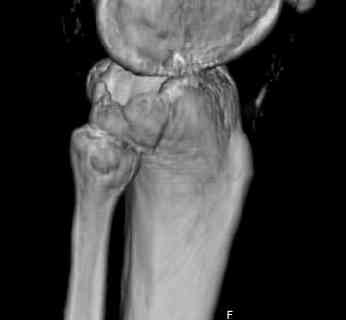

Здравствуйте, уважаемые коллеги!Подскажите, пожалуйста, какой выбрать доступ и способ фиксации при импрессионном переломе заднего отдела наружного мыщелка большеберцовой кости. Женщина 40 лет, травму получила 02.01.2008, катаясь на горных лыжах.Есть ли здесь необходимость использовать задний доступ, или можно справиться через наружный? Есть ли шансы сделать закрыто - под ЭОП через медиальное "окошко" поднять забойником суставную поврехность? Какой лучше использовать фиксатор?Спасибо.

центральная импрессия, а при ипрессии с краевым переломом - после приподнимания импрессии опорная (Butress) пластина, как на снимке.

In this situation, where the fragment is posterolateral, one needs a posterior approach, either as described by Timothy Bhatacharya et al in 2005 in JOT, which involves taking down the medial head of the gastrocnemius, or the Lobenhoffer paper which involves a transfibular approach.

would anyone consider an anterolateral approach with a sagital osteotomy just lateral to midline?

this would give access to the impacted posterior region. then "backgraft", and fix the osteotomy

fragment with a standard anterolateral plate. thanks.